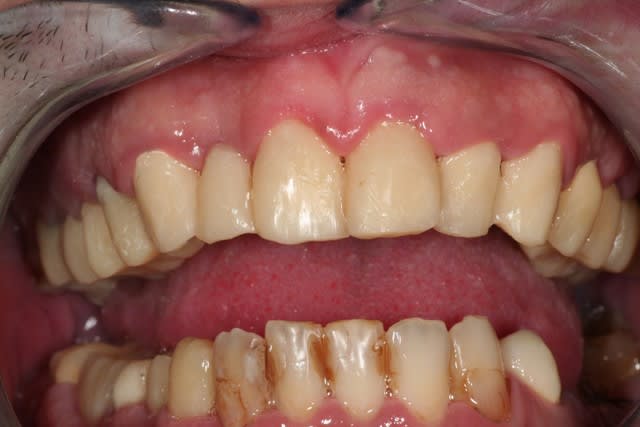

salut les petits clous...

voilà, je me suis remis un peu au boulot.

voici quelques images....

juste une remarque: pour l'instant je suis à la même DV.